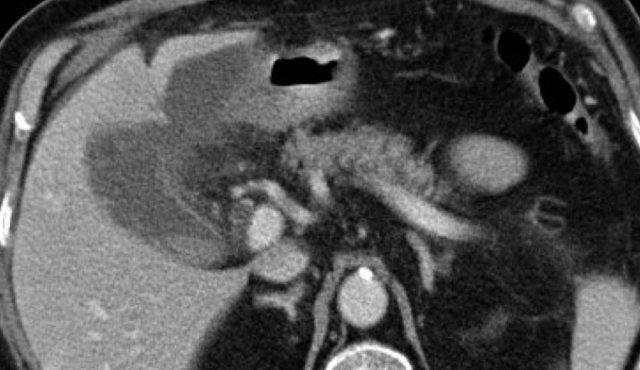

These images are of an obese patient with acute RUQ pain for 6 hours. CRP 2 .

US shows a large gallbladder with sludge, no stones were visualized.

Compression of the gallbladder is unreliable due to the high position under the right costal arch.

No other US abnormalities.

CT, performed the same day, shows a large gallbladder with only discrete pericholecystic changes and no other explanation for the symptoms.

The next day CRP is 105 and repeated non-contrast CT shows a fuzzy corona around the gallbladder.

Subsequent surgery confirmed early acute cholecystitis due to a small stone in the cystic duct.